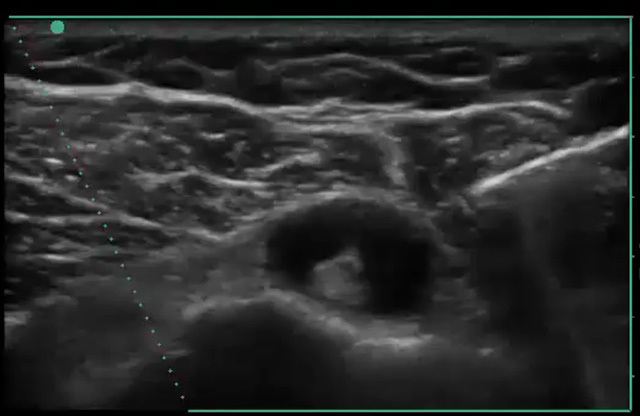

Shoulder Biceps Tendon Sheath Injection Image